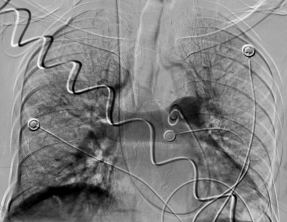

肺動(dòng)脈左右分支大量血栓(左邊血栓說明) 下腔靜脈大范圍血栓(濾器置入攔截)(右圖血栓說明)

十堰市人民醫(yī)院介入科迅速科內(nèi)會(huì)診,并制定周密、詳細(xì)的介入治療方案。術(shù)中,專家團(tuán)隊(duì)嚴(yán)格按照手術(shù)方案進(jìn)行手術(shù),第一步完成下腔靜脈濾器,攔截血栓,放射介入專家陳光斌、謝興武、李江山等專家團(tuán)隊(duì)全力以赴,在下腔靜脈情況不明,有無(wú)血栓無(wú)法再看的情況下,果斷采取從頸靜脈穿刺,下腔靜脈手推造影。而患者的嚴(yán)重程度讓多位專家倒吸一口涼氣,只見下腔靜脈中下段大塊血栓形成,栓頭鄰近雙腎靜脈,血栓隨時(shí)可能脫落。

見此情形,放射介入專家小心翼翼操作,將濾器死死卡住血栓頭,接下來就是第二步:完成肺動(dòng)脈開通。重癥醫(yī)學(xué)科專家加大氧流量,血管活性藥物穩(wěn)定血壓,為介入操作創(chuàng)造時(shí)間,同時(shí)介入專家豬尾巴導(dǎo)管上、導(dǎo)引導(dǎo)管上,不停進(jìn)行各段抽吸、取栓,經(jīng)過一個(gè)小時(shí)的精細(xì)操作,功夫不負(fù)有心人,雙肺動(dòng)脈干通了,主要肺動(dòng)脈分支通了,肺血管網(wǎng)明顯增多了,患者的情況也好轉(zhuǎn)了起來!也就意味著第二步操作成功!隨后的第三步,介入專家對(duì)下肢血栓進(jìn)行了抽吸、取栓,并置入溶栓導(dǎo)管進(jìn)行持續(xù)藥物灌注溶栓。又經(jīng)過兩個(gè)小時(shí),在兩科的密切合作下,整臺(tái)手術(shù)順利完成。

手術(shù)完幾個(gè)小時(shí),當(dāng)天下午就傳來好消息,患者生命體征明顯好轉(zhuǎn)。在放置導(dǎo)管的第三天,患者再次來介入科造影,發(fā)現(xiàn)肺栓塞基本消失,下肢血栓明顯消失,濾器繼續(xù)卡住下腔血栓!經(jīng)過多學(xué)科努力,通過綜合介入各種手段,重癥肺栓塞患者搶救成功!